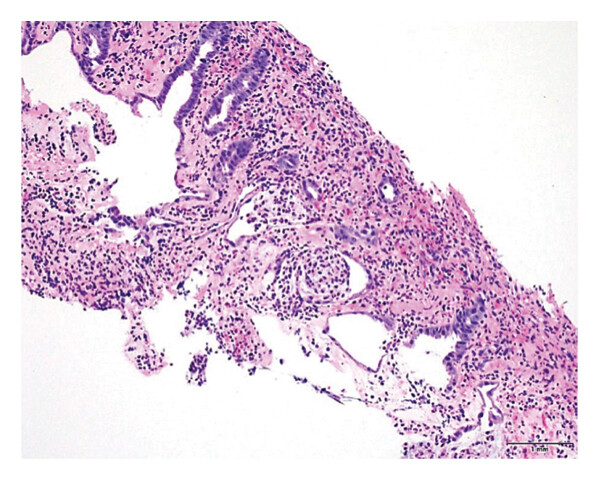

С помощью биопсии был выявлены признаки колита инфекционной или лекарственной этиологии (рис. 3).

Рисунок 3. Биопсийный образец образования в слизистой оболочке восходящего отдела ободочной кишки, где заметны воспалительные и ишемические изменения (небольшие железы, отечная и фибринозная собственная пластинка с образованием псевдомембран), ГЭ;×200.